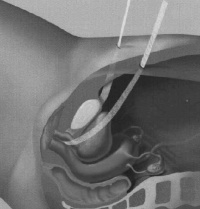

4.尿道膀胱造影 正常膀胱后角应为90°~100°,上尿道轴与立位的垂直线,形成1 个约30°的尿道倾斜角,膀胱颈高于耻骨联合下缘。压力性尿失禁时,膀胱尿道后角消失,膀胱颈低于耻骨联合下缘,尿道倾斜角增大,膀胱颈部呈漏斗状并下垂,尿道轴发生不同程度的向下、向后旋转。Green 将它分为两型:Ⅰ型,尿道轴线正常,但后尿道膀胱角增大;Ⅱ型,膀胱后尿道角消失,腹压增加时尿道下降、扭曲使尿道倾斜角增加,尿道倾斜角>45°,有时>90°,膀胱颈有关支撑组织薄弱,症状严重,治疗困难。此后McGurie 提出将与尿道固有括约肌功能下降相关的压力性尿失禁命名为Ⅲ型。

1.非手术治疗:会阴部肌肉训练,收缩肛门及尿道括约肌,每日三回,每回做15-30次,至少半年。局部注射Tefkon膏,老年患者可给予雌激素制剂。 2.手术治疗:目前以膀胱颈悬吊术的效果最好,膀胱颈悬吊术的方法有经耻骨后膀胱颈及尿道悬吊术及经阴道膀胱颈部悬吊术,以增加膀胱颈部与尿道的角度。